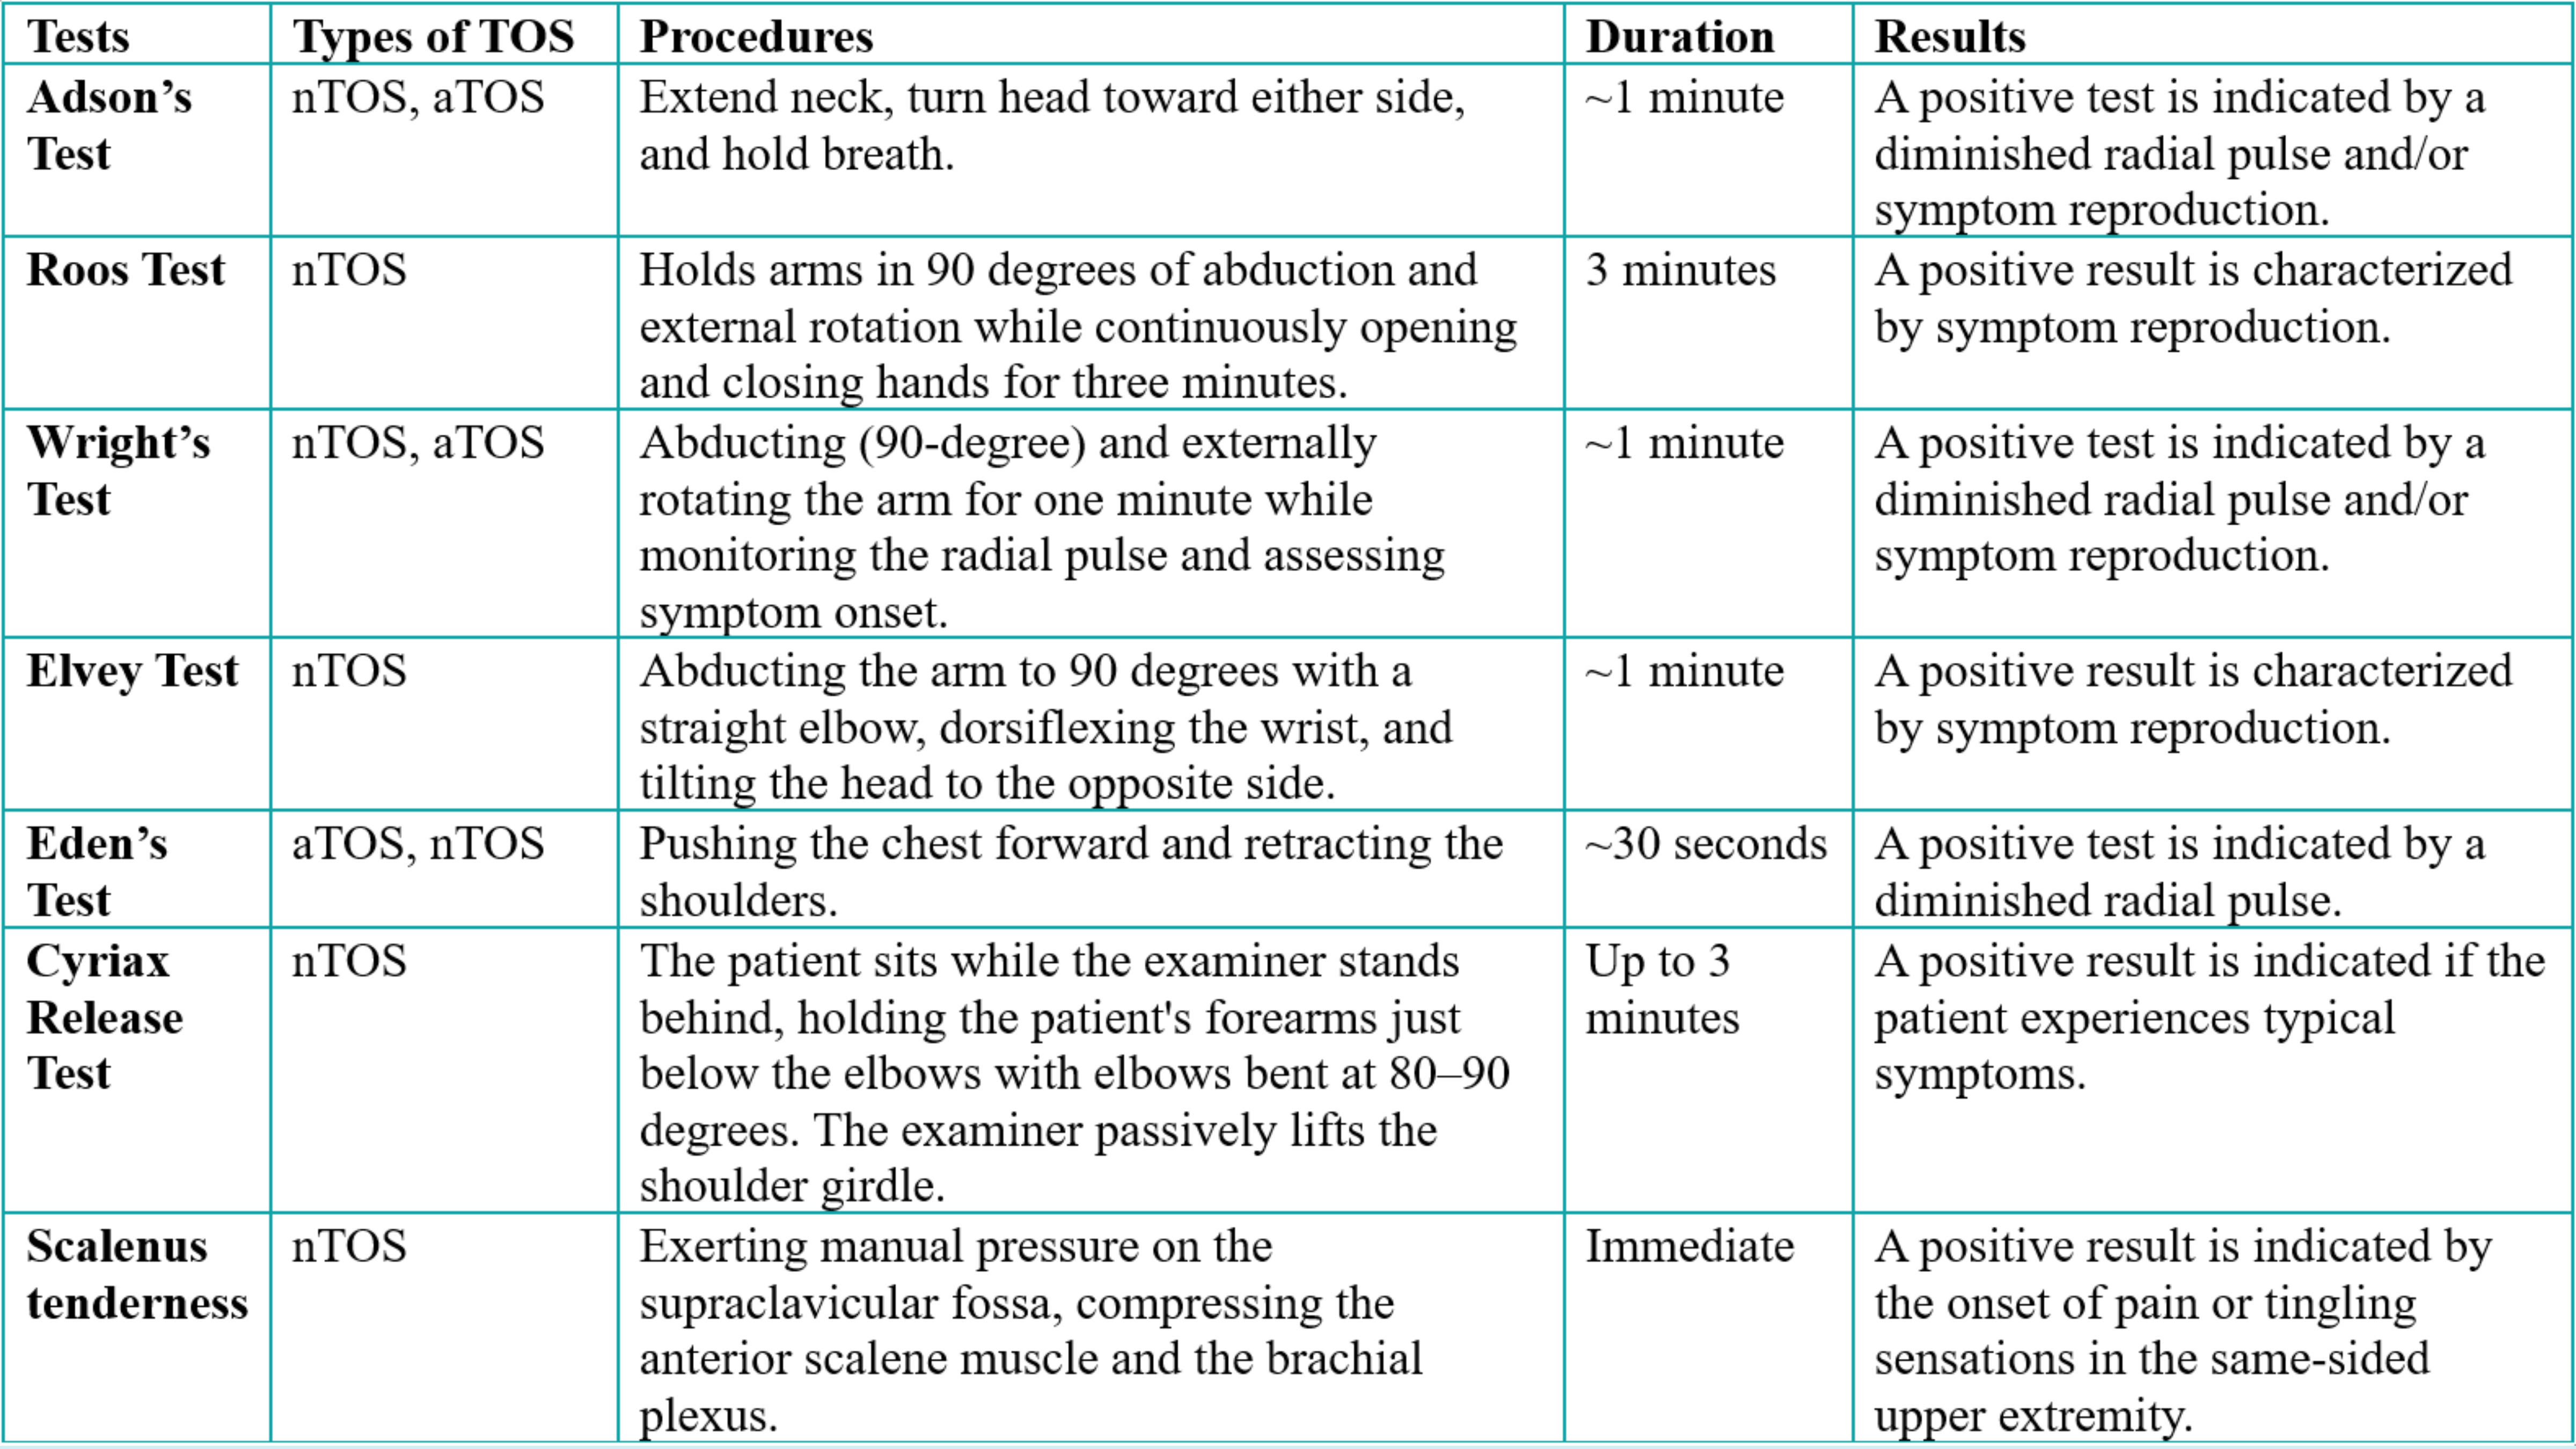

Gender Male Female Non-Identified |

505 (50.40%) 496 (49.50%) 1 (0.10%) |

|

Age (year) 3 – 18 19 – 30 31 – 40 41 – 50 51 – 60 61 – 70 > 70 N/A Median (QR) |

63 (6.29%) 52 (5.19%) 47 (4.69%) 34 (3.39) 18 (1.80%) 28 (2.79%) 20 (2.00%) 740 (73.85%) 35 (19–51) |

|

Clinical presentations* Pain Fever Shortness of breath Cough Asymptomatic Others N/A |

189 (18.86%) 66 (6.59%) 41 (4.09%) 27 (2.69%) 51 (5.09%) 42 (4.19%) 616 (61.48%) |

|

Diagnostic findings |

|

|

Hydatid serology Positive Negative N/A CT scan Ultrasound MRI X. ray Echocardiogram N/A |

139 (13.87%) 31 (3.09%) 832 (83.03%) 806 (80.44%) 475 (47.40%) 168 (16.77%) 69 (6.88%) 23 (2.29%) 105 (10.48%) |

|

Quantity of the cyst Single cyst Multiple cysts N/A |

466 (46.51%) 203 (20.26%) 333 (33.23%) |

|

Cyst status Patients with intact cysts Patients with ruptured cysts Patients with intact and ruptured cysts N/A |

100 (9.98%) 97 (9.68%) 6 (0.60%) 799 (79.74%) |

|

Type of treatment Surgical intervention Percutaneous treatment Medical treatment None N/A |

639 (63.77%) 75 (7.49%) 31 (3.09%) 2 (0.20%) 255 (25.45%) |

|

Medication Albendazole Albendazole & Praziquantel Mebendazole None N/A |

275 (27.44%) 9 (0.90%) 1 (0.10%) 26 (2.59%) 691 (68.96%) |

|

Follow up < 1 month – 6 months > 6 months – 1 year > 1 year – 2 years > 2years – 4 years > 4 years – 7 years > 7 years N/A |

347 (34.63%) 25 (2.50%) 27 (2.69%) 13 (1.30%) 5 (0.50%) 2 (0.20%) 583 (58.18%) |

|

Recurrence Yes No N/A |

26 (2.59%) 566 (56.49%) 410 (40.92%) |

|

Death Yes No N/A |

17 (1.70%) 666 (66.47%) 319 (31.83%) |

|

* Some patients had multiple clinical presentations, CT scan: computed tomography scan, MRI: magnetic resonance imaging, N/A: not available |

|

Discussion

Hydatidosis is most common in countries with extensive livestock industries but has recently become a significant global health issue due to rising immigration and travel [117, 232]. The disease is prevalent in Peru, Chile, Argentina, Uruguay, southern Brazil, the Mediterranean basin, Central Asia, western China, and East Africa. It remains absent in Antarctica and has been successfully eradicated through comprehensive control measures in Iceland, New Zealand, Tasmania, the Falkland Islands, and Cyprus [233]. In the present study, Spain unexpectedly showed the highest percentage of CE cases, with 36.13%, followed by China (26.95%) and Turkey (12.77%), collectively accounting for nearly 75% of all reported cases. Spain is known to be an endemic country for CE, but this unusually high percentage may be attributed to the fact that Spain has advanced healthcare infrastructure and diagnostic capabilities, which could lead to more accurate identification and reporting of CE cases. In contrast, in many developing countries, where resources and diagnostic tools may be limited, CE cases might be underreported or misdiagnosed [234]. This diversity underscores the importance of diagnostic and reporting capabilities when comparing CE prevalence across countries with differing healthcare systems. Regarding continental distribution, Asia represented 48.60% of cases, with Europe closely following at 45.91%. This distribution demonstrates that CE is not limited to traditionally endemic regions in developing countries but is also present in developed countries.

Studies have identified the liver as the most common site for hydatid cysts, accounting for 75% of cases, followed by the lungs (15%) and the brain (2%) [3]. Furthermore, cysts can form in various other organs and structures, including the abdominal and pleural cavities, kidneys, spleen, bones, eyes, ovaries, testes, and pancreas [233]. The current study's findings confirm that the liver remains the most frequently affected organ (73%), with the lungs (11%) being the second most common site, consistent with the literature. However, the current study found that the kidneys, heart, and muscles were more frequently affected than the brain (2%–4% of cases). This contrasts with previous studies identifying the brain as the third most commonly affected organ [3, 235].

The European Centre for Disease Prevention and Control (ECDC) indicates that the occurrence of echinococcosis does not display a notable difference between genders, presenting a nearly balanced male-to-female ratio of 1.1:1 [236]. This finding aligns with the results of the present study, where the gender distribution among the cases was nearly equal, with males comprising 50.39% and females 49.50%, yielding a male-to-female ratio of approximately 1:0.98. However, Otero-Abad et al. reported that women are more susceptible to echinococcosis than men. This increased risk was linked to their more significant participation in household activities, such as food preparation and caring for pets, heightening their exposure to infected dogs, soil, and vegetables [237].

Moro et al. stated that only 10-20% of CE cases are identified in patients under 16 years old [238]. This is likely because CE is slow-growing and often asymptomatic, with most liver and lung cysts becoming symptomatic and diagnosed in adults. In contrast, in the current study, the highest prevalence of CE was observed in the pediatric age group of 3-18 years, with a rate of 24.05% among the 262 patients with available age data. This difference may be attributed to advancements in early CE diagnosis and the fact that most cases in this study were based on case reports. However, it is important to note that age data were unavailable for 73.85% of patients, which could potentially influence the observed distribution, as the missing data might disproportionately affect certain age groups and alter the findings. The next highest prevalence was in the 19-30 years (19.85%) and 31-40 years (17.94%) age groups, indicating that CE is also common among young and middle-aged adults. In contrast, a study in Western Romania found the highest prevalence in individuals aged 50-59 years (21.7%) [239], while the current study showed a much lower prevalence in the 51-60 years age group (1.80%). These differences may be attributed to regional variations in risk factors, such as livestock exposure, environmental conditions, and access to healthcare, all of which can influence the age distribution of CE.

The clinical presentation of CE is highly variable, primarily influenced by factors such as the cyst's location, size, and condition. As CE cysts tend to grow slowly over time, they often result in a prolonged asymptomatic phase. Symptoms usually appear when the cysts reach a size that causes pressure effects or functional impairment in the affected organ [238]. Several studies highlight the differences in asymptomatic rates across various organ involvements. Ciftci et al. reported that 52.9% of patients with renal hydatid cysts were asymptomatic, indicating that cysts in the kidneys may remain unnoticed for extended periods until they cause local complications or are incidentally discovered [104]. In contrast, Akhan et al. found a higher rate of asymptomatic cases, 73.68%, among patients with liver hydatid cysts, suggesting that hepatic involvement might often go undetected, potentially due to the liver's capacity to accommodate growth without immediate symptoms [149]. In the present study, clinical presentation for 386 patients was available, and a much lower asymptomatic rate of 13.21% was observed. This discrepancy could be due to differences in cyst locations. It is possible that a higher proportion of patients in this study presented with symptoms due to the cysts being located in more clinically sensitive areas. Additionally, the lower asymptomatic rate might reflect a population with more advanced or larger cysts at the time of diagnosis, thereby increasing the likelihood of symptomatic presentation.

Early detection of CE can greatly improve the success of its management and treatment [240]. The definitive diagnosis of CE typically relies on imaging techniques such as radiology, ultrasound, computed tomography (CT), and magnetic resonance imaging (MRI) [241]. Serological tests like enzyme-linked immunosorbent assay (ELISA) offer high specificity for detecting HD, but a positive result does not accurately reveal the cyst’s location. Conversely, imaging methods provide detailed visualization, identifying cysts at specific sites. This limitation emphasizes combining serological testing with imaging to diagnose and precisely locate the hydatid cyst [242]. In the present study, among the 170 patients with CE who had serological test results available, 18.23% tested negative.

Preventing CE relies on disrupting E. granulosus's life cycle. For instance, regular screening and treatment of infected dogs have effectively eradicated the disease in endemic regions. Additional control measures include restricting the feeding of home-slaughtered livestock to dogs and vaccinating intermediate hosts, such as sheep [243]. Community education plays a crucial role in preventing disease spread by raising awareness of the risks associated with infected animals and contaminated environments. Ongoing monitoring and collaboration among healthcare providers, veterinarians, and the community are essential for early detection and prompt intervention [244].

One limitation of this study is the predominance of case reports among the included studies. While these reports offer valuable insights into rare occurrences, they are inherently limited by small sample sizes, and potential selection bias. As a result, the findings may not be easily generalized to broader populations, and the ability to draw strong conclusions. Further research is needed to address the diagnostic challenges of CE in non-endemic regions, with a focus on improving early detection and treatment. Future studies should prioritize increasing healthcare professionals' knowledge, refining diagnostic processes, and evaluating the effectiveness of serological and imaging tools in regions with low disease prevalence.

Conclusion

Hydatidosis persists as a significant global public health concern, impacting both developing and developed countries. The liver and lungs remain the primary sites of infection. Preventive strategies, including regular animal screening and enhanced public health education, are essential for controlling the spread of the disease.

Declarations

Conflicts of interest: The author(s) have no conflicts of interest to disclose.

Ethical approval: Not applicable.

Consent for participation: Not applicable.

Consent for publication: Not applicable.

Funding: The present study received no financial support.

Acknowledgments: None to be declared.

Authors' contributions: HAN, BAA, FHK, and HOA: major contributors to the conception of the study, as well as the literature search for related studies, and manuscript writing. SMA, SHM, RQS FA, YMM and DAH: Literature review, design of the study, critical revision of the manuscript, and processing of the tables. TMM, MNH, HAH, SHK, KKM, DAO, SHS and KAN: Literature review, data analysis and interpretation. All authors have read and approved the final version of the manuscript.

Use of AI: AI was not used in the drafting of the manuscript, the production of graphical elements, or the collection and analysis of data.

Data availability statement: Not applicable.

Blunt Chest Trauma and Chylothorax: A Systematic Review

Hiwa O. Abdullah, Fahmi H. Kakamad, Harem K. Ahmed, Bnar J. Hama Amin, Hadi M. Abdullah, Shvan H....

Abstract

Introduction: Although traumatic chylothorax is predominantly associated with penetrating injuries, instances following blunt trauma, as a rare and challenging condition, are being increasingly documented. This study aims to systematically review the reported cases of blunt chest traumatic chylothorax (BCTC) and provide comprehensive insights into the condition.

Methods: Related studies published until December 11, 2024, were identified through Google Scholar. All studies documenting instances of BCTC, without restriction on cause or patient demographics, were included. Studies were excluded if they focused on chylothorax caused by penetrating injuries, their content was unretrievable, they were review articles, or they were published in blacklisted journals.

Results: Sixty-five eligible studies, encompassing 69 cases of BCTC, were included in the review. It predominantly affected males (73.91%), with patient ages ranging from 11 months to 84 years old. The most common clinical findings were dyspnea (47.83%) and abnormal auscultation or percussion (34.78%), with road traffic accidents as the primary cause (59.42%). Unilateral chylothorax was found in 72.46% of cases, bilateral chylothorax occurred in 27.54%, and pleural effusion was the most frequent radiological finding (55.07% in X-ray and 33.33% in computed tomography). Treatment typically included drainage (94.20%), parenteral nutrition (50.72%), and thoracic duct closure (39.13%). Most patients achieved complete recovery (89.85%), and six cases (8.70%) died.

Conclusion: The condition is rare and complex, underscored by the wide variability in patient demographics, clinical presentations, chylothorax onset, and management approaches. Given the challenges posed by limited evidence, the findings emphasize the need for early recognition and individualized management strategies.

Introduction

Chylothorax is a rare condition characterized by the accumulation of chyle in the pleural cavity caused by a disruption of the thoracic duct [1]. Chyle is an opalescent fluid that consists of triglycerides, chylomicrons, proteins, electrolytes, immunoglobulins, and fat-soluble vitamins, transported from the gastrointestinal system into the bloodstream by the thoracic duct. It makes up about 1-3% of total body weight in adults. Chylothorax was initially described by Bartolet in 1633 and later reported in the literature by Quinke in 1875 [1,2]. It is categorized into congenital, neoplastic, traumatic, and miscellaneous forms. The most common cause is malignancy, which leads to obstruction of the thoracic duct, while traumatic chylothorax is typically iatrogenic, resulting from surgical procedures or catheter placement. Penetrating trauma is the usual cause of traumatic chylothorax, while blunt trauma is considered an infrequent cause [1,2]. It may also develop due to chest compression or changes in intrathoracic pressure, such as during coughing or persistent vomiting [2].

The incidence of chylothorax is about 0.2% following blunt thoracic trauma and 0.9% after penetrating trauma. Bilateral chylothorax resulting from blunt trauma, mainly when no other injuries are evident, is an infrequent but severe complication [3]. Without prompt treatment, chylothorax can lead to serious complications, such as cardiopulmonary distress and significant nutritional deficiencies, with a high mortality rate of up to 15.5% [2-4]. Although traumatic chylothorax is predominantly associated with penetrating injuries, instances following blunt trauma have been increasingly documented, highlighting the need for awareness among healthcare providers regarding this potential complication [5,6]. This study aims to systematically review the reported cases of blunt chest traumatic chylothorax (BCTC) and provide comprehensive insights into the condition.

Methods

Literature search

The study followed the Preferred Reporting Items for Systematic Reviews and Meta-Analyses (PRISMA) guidelines. Related studies published until December 11, 2024, were identified through Google Scholar using a search strategy that combined the following keywords with the “allintitle” and “including citation” features: (blunt trauma chylothorax), (blunt thoracic trauma chylothorax), (blunt thoracic injury chylothorax), (blunt chest injury chylothorax), (blunt torso trauma chylothorax), (blunt thoracic duct trauma), (blunt thoracic duct injury) and (traumatic chylothorax). The search was limited to English-language publications.

Eligibility criteria

All studies or reports documenting instances of BCTC, without restriction on cause or patient demographics, were eligible for inclusion. Studies were excluded if they focused on chylothorax caused by factors other than blunt chest trauma, if their content was unretrievable, if they were review articles, or if they were published in blacklisted journals. The legitimacy of the studies was verified by cross-referencing with widely recognized predatory journal checklists [7].

Study selection

First, an author conducted a literature search using the specified keywords and collected the relevant results. The titles and abstracts of the identified studies were then screened to exclude duplicates, non-English studies, and those unrelated to the study objective. Full-text screening was conducted for studies that passed the initial filtration, excluding those with unretrievable content or irrelevant study designs, such as reviews. This step was supervised by two authors, who independently reviewed each study. Finally, the remaining studies underwent legitimacy filtering.

Data extraction

The collected data encompassed various parameters, including the first author's name, year of publication, patient demographics, clinical manifestations, causes of chylothorax, chyle volume and content, the onset of chyle production, diagnostic methods, ICU admission status, treatment modalities, outcomes, and follow-up.

Statistical Analysis

The extracted data were organized in an Excel sheet (2019) and analyzed descriptively using the Statistical Package for the Social Sciences (SPSS, v. 27, IBM Co.). The results were presented in frequencies with percentages, means with standard deviation, and ranges.

Results

Study identification

A systematic search yielded 201 studies, all of which were case reports. After removing duplicates (16) and non-English articles (17), 168 titles and abstracts were screened. Fifty-five case reports were excluded due to irrelevance, and full-text evaluation of the remaining 113 case reports led to the exclusion of an additional 42. Furthermore, six articles were excluded for being published in warning-listed journals. Consequently, 65 eligible case reports, encompassing 69 cases of BCTC, were included in the review [1-6,8-66] (Tables 1 and 2). The identification process is outlined in a PRISMA flowchart (Figure 1).

|

First author, year [Reference] |

Country |

Age (year) |

Gender |

CFP |

Cause |

SOC |

Amount of chyle (ml)/day* |

COAP (day) |

Biochemical content of chyle |

|

Harvey, 2024 [5] |

USA |

60 |

F |

Chest pain, multiple rib fractures |

RTA |

Left |

<500 |

2 |

Triglycerides |

|

Burduniuc, 2023 [2] |

Czech Republic |

70 |

F |

Blunt injury |

Fall on stairs |

Right |

>1000-2000 |

3 |

Protein, cholesterol, triglycerides |

|

Dung, 2023 [14] |

Vietnam |

32 |

M |

Thoracic spine injury, paraplegia |

RTA |

Right |

>1000-2000 |

At once |

Cholesterol, triglycerides |

|

Kim, 2023 [4] |

South Korea |

45 |

M |

Hemodynamically unstable, chest discomfort, multiple fractures, hemopneumothorax |

Crushed by a 2-ton metal frame |

Left |

>1000-2000 |

1.66 |

Triglycerides |

|